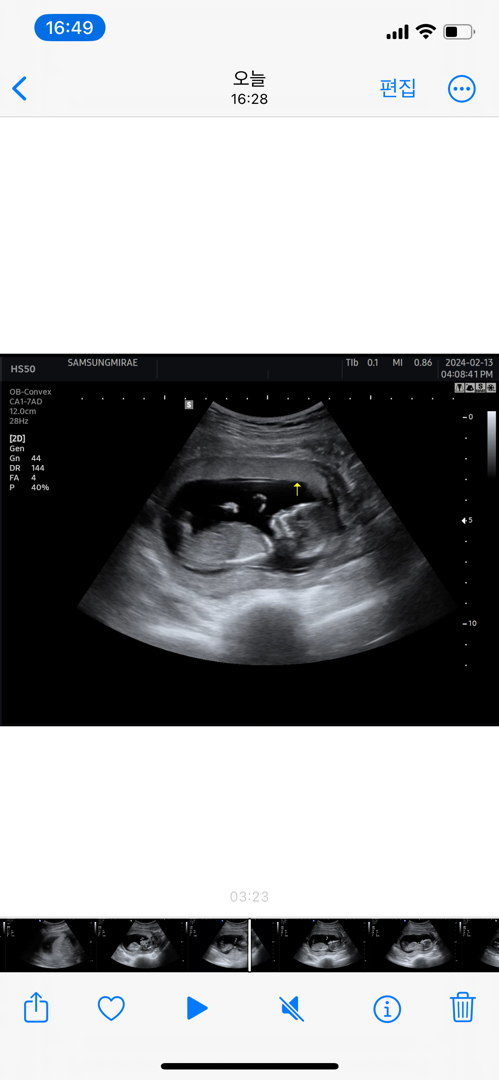

12주 각도법 봐주세용

12주 각도법 봐주세요~ 계속 봐도 모르겠네요ㅠㅠ